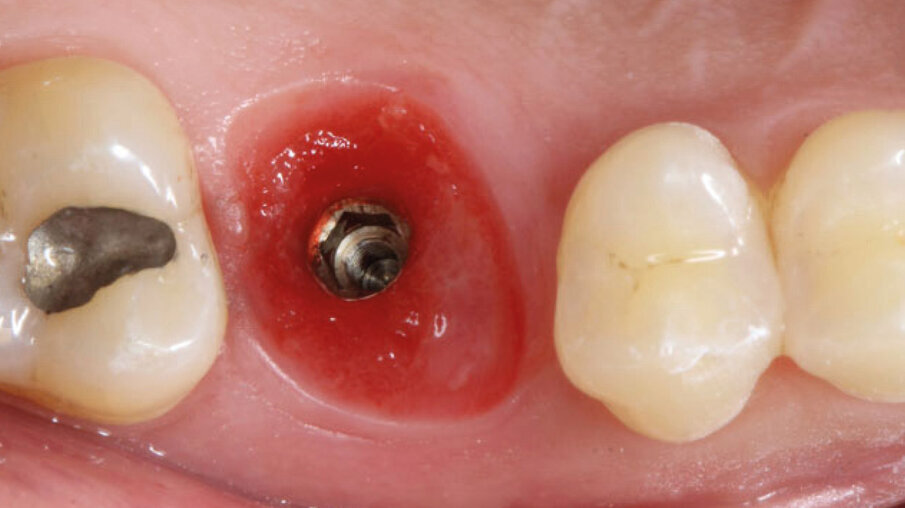

Dopo l’esecuzione dell’anestesia locale, il dente è stato rimosso e l’alveolo pulito dai residui del legamento parodontale. È stato inserito l’impianto (Zimmer TSV, Zimmer, Parsippany) 4.1 x 11,5 TSVM posizionato seguendo il protocollo consigliato dal produttore (Fig. 3). L’impianto è stato inserito a livello della cresta alveolare. È stato avvitato lo scan-abutment (Zfx Intrascan Matchholder, Zfx,). È stata rilevata un’impronta ottica intra-operatoria dell’emiarcata in cui è stato posizionato l’impianto con lo scan abutment (Fig. 3). Il gap tra l’osso vestibolare e l’impianto è stato riempito con Bio-Oss (Geistlich Pharma) (Fig. 4). Al termine della chirurgia è stato progettato e fresato il provvisorio, che è stato applicato appena pronto, dopo aver inserito la matrice in collagene volumetricamente stabile Fibro-Gide (Geistlich Pharma) precedentemente imbibita con il gel a base di polinucleotidi e acido ialuronico Regenfast (Officine Bio-Farmaceutiche Mastelli), al di sotto della vite stessa (Figg. 5, 6). Data l’accuratezza della vite non sono state necessarie suture. Al termine della procedura è stata eseguita una radiografia di controllo (Fig. 7).

Fig. 4 - Inserimento implantare con zappatura del gap con Bio-Oss.